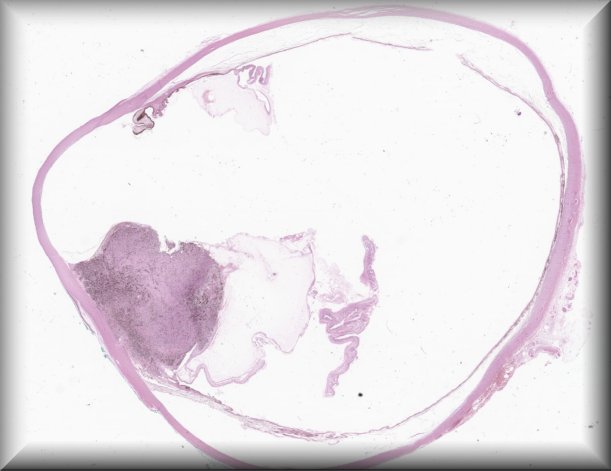

Paul van der Valk (Amsterdam): Orbital tumour. |